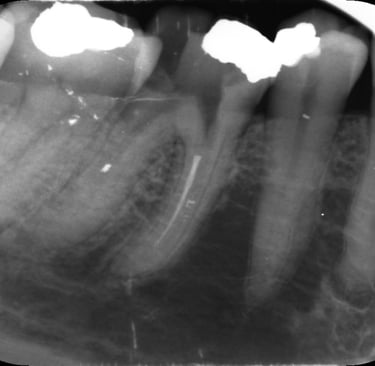

Case Study: Consent Failure in a Root Canal Treatment

We recently helped a woman who underwent a root canal at a dental practice in Bolton.

She was never warned that metal filings could break off, become embedded in her gum, or that there was a risk of ultimately losing the tooth.

All of that happened.

She experienced ongoing pain and swelling. She later told us she would never have agreed to the procedure had she been properly warned about the risks.

We made a claim against the dentist’s insurers and secured a £10,000 settlement — even though the treatment itself wasn’t negligent.